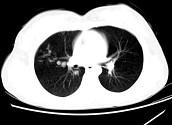

问题 女,24岁,HCG阳性,咯血2天,行胸部CT扫描如图,其最可能的诊断为 ( )

选项 A.转移性绒癌 B.肺部感染 C.肺结核 D.肺血管瘤 E.肺淋巴管肌瘤

答案 A